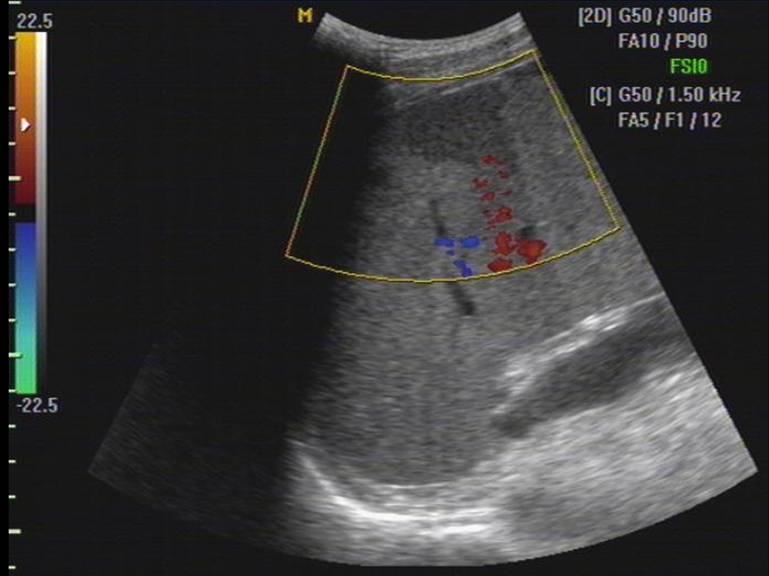

彩色多普勒

脾挫伤和血肿内无血流信号

CDFI梗塞区缺乏血流灌注因而不显示彩色血流信号。